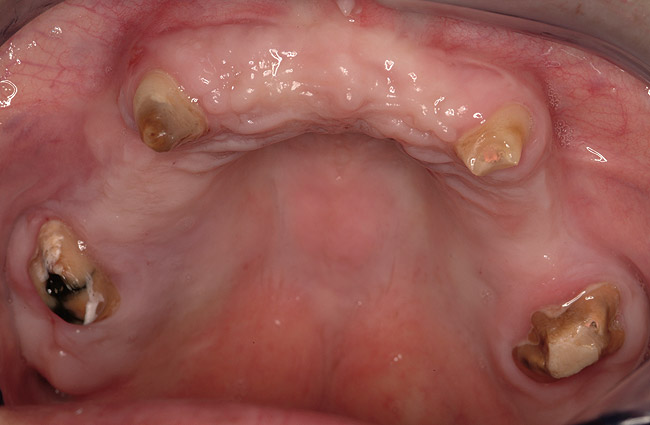

Figure 14  Severe periodontitis and periodontal abscess on the facial aspect of tooth Nos. 7 and 8. All maxillary teeth were hypermobile and the patient was symptomatic in the anterior sextant.

Figure 14

Case Two

A 46-year-old woman presented with advanced chronic periodontitis and had already lost several maxillary and mandibular teeth (Figure 13 and Figure 14). She initially complained of pain in the maxillary anterior sextant, where a draining sinus tract between tooth Nos. 7 and 8 was evident. The patient desired a fixed restoration and was unwilling to wear a removable prosthesis, even on a temporary basis, if possible. It was decided that tooth Nos. 2, 6, 11, and 15 would be retained to support a fixed, provisional bridge, while the patient’s remaining teeth would be extracted and bone augmentation performed, followed by implant placement (Figure 15). Extraction of the maxillary teeth with the exception of these four teeth was done to simplify provisionalization.